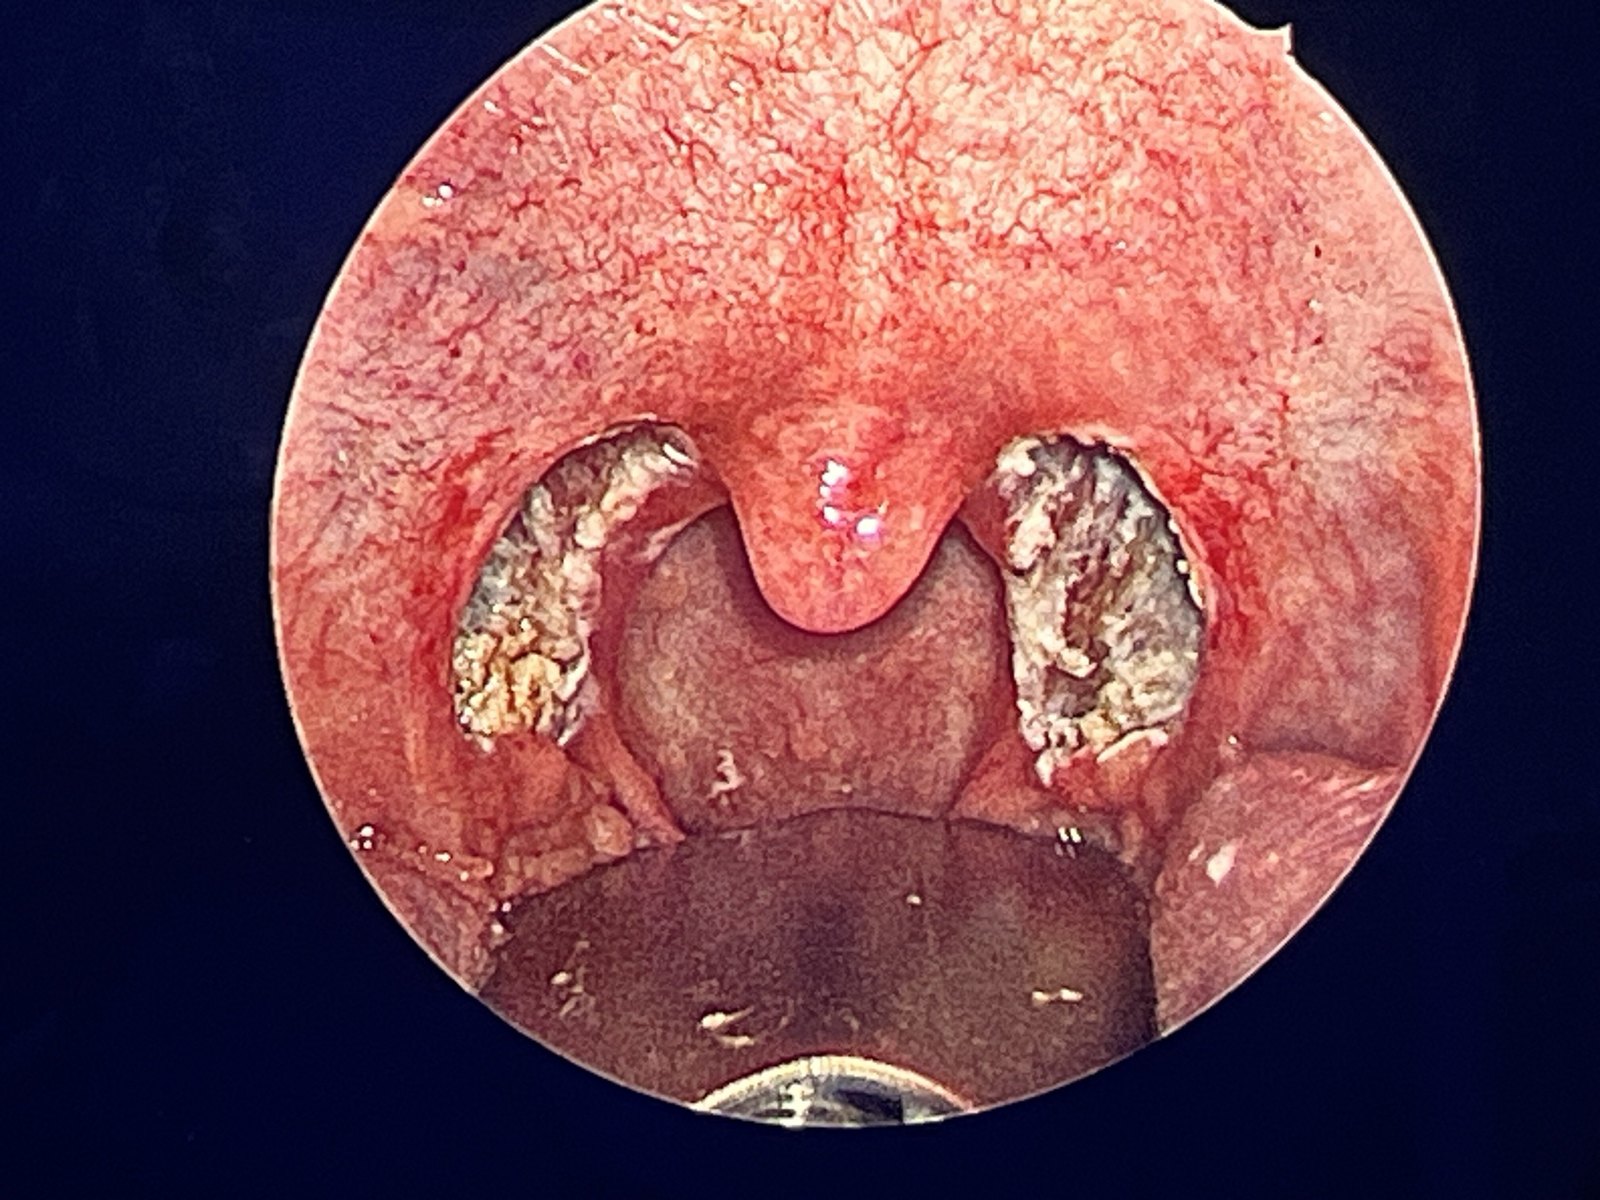

下鼻甲肥大鼻息肉等,费用大概在1000~3000元不等针对扁桃体肥大的手术,如咽部粘膜松弛舌根扁桃体增生,具体费用需根据手术情况确定,但腭扁桃体切除手术腭咽成形术舌根扁桃体部分消融等手术的价格一般在1000~2000元左右如果选择做等离子手术,费用会相对较高,一般在4000~5000元左右。